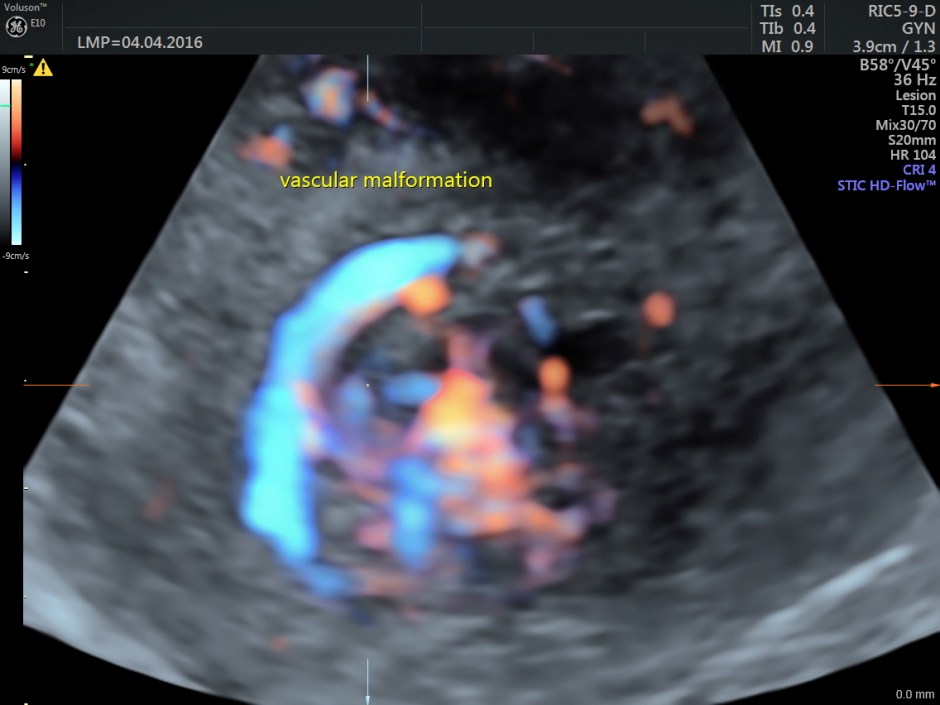

The following are the different sections of the Power Doppler reconstruction images of the trans-vaginal scan.

The following are the reconstructed 3D Power Doppler images.

The ultrasound diagnosis was a vascular malformation in the uterus .She was referred to an interventional radiologist,who did a CECT the next day.

Typically shows serpiginous/tubular anechoic structures within the myometrium with a low resistance (RI ~0.2-0.5), high velocity flow pattern on colour Doppler interrogation.